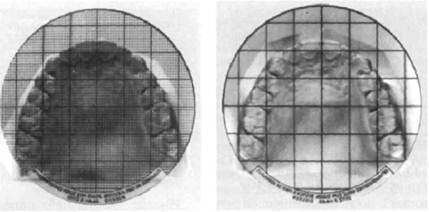

Симметроскопия. С помощью этого метода изучают место расположения зубов в трансверсальном и сагиттальном направлениях. Орто-крест (ортодонтический крест) применяют для экспресс-диагностики. Он представляет собой прозрачную пластину, на которую нанесен крест с миллиметровыми делениями или миллиметровая сетка с делениями через 1—2 мм. Пластину накладывают на гипсовую модель верхней челюсти, ориентируя крест по срединному небному шву, и затем изучают расположение зубов по их отношению к срединной и поперечной линиям (рис. 13.24).

Фотосимметроскопия представляет собой метод симметроскопии диагностических моделей челюстей с последующим их фотографированием в определенном режиме. Фотографию моделей челюстей со спроецированной на нее миллиметровой сеткой в дальнейшем изучают и проводят измерения.